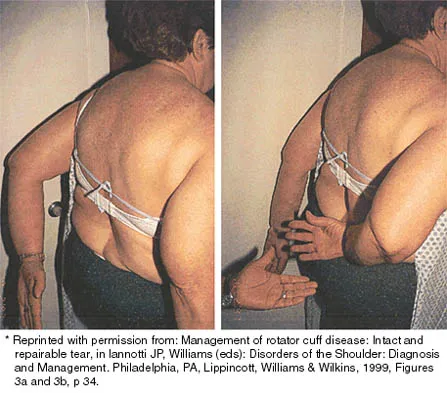

A 43-year-old bus driver sustains a hyperextension injury to her arm and shoulder 4 months after undergoing an open Bankart repair. Examination reveals increased external rotation, anterior shoulder pain, and internal rotation weakness. Her examination also reveals the findings shown in Figure 44. What is the most likely diagnosis?